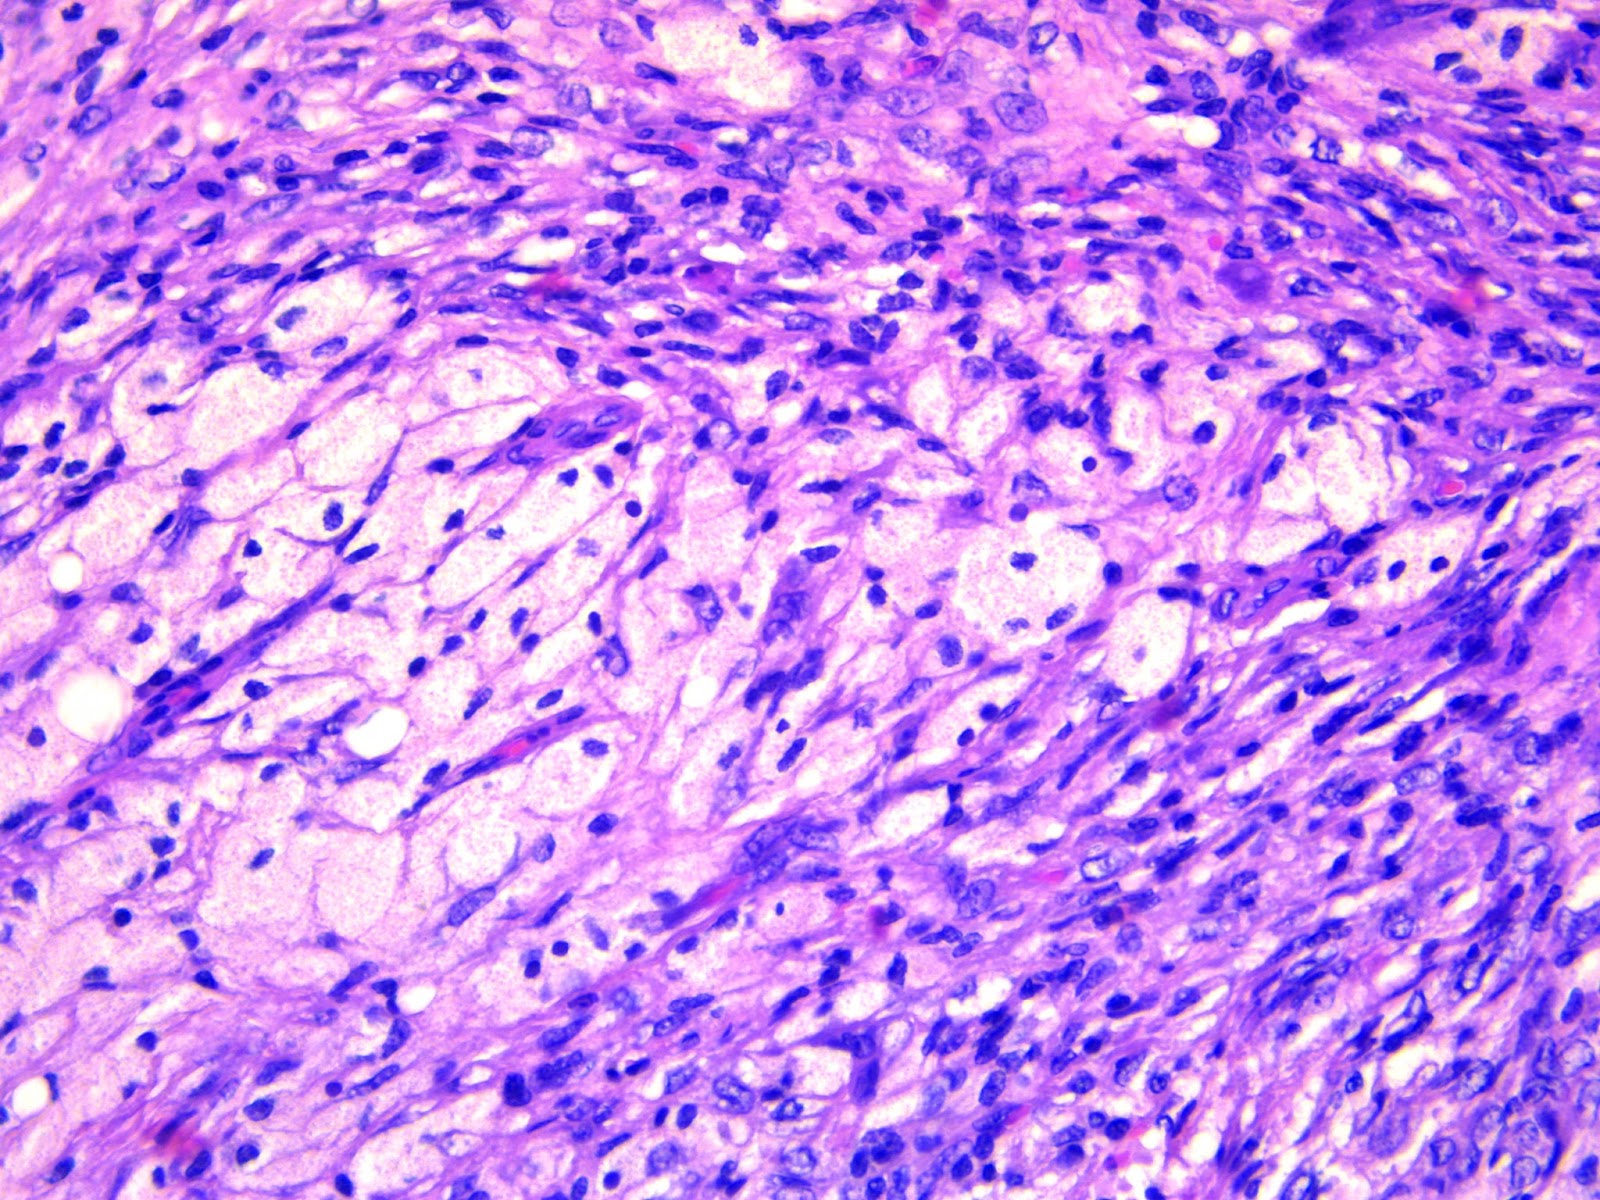

Infantile fibrosarcoma / Fibrosarcoma infantil t(12:15)

Paciente de 3 meses con tumor en brazo, los cortes histológicos muestran neoplasia fusocelular, con células que se disponen juntas formas haces cortos que se cruzan entre ellos, en patrón de "espinas de pescado", la atipia celular es moderada y la actividad mitósica es alta.